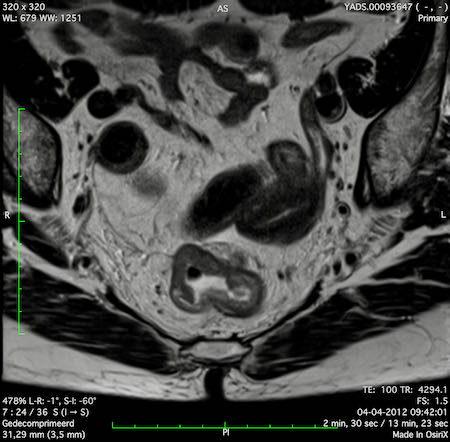

Hình ảnh

Các hình ảnh được cung cấp cho thấy ung thư biểu mô tế bào nhẫn với tình trạng dày lan tỏa thành trực tràng, hình ảnh bia bắn điển hình, và sự xâm lấn mỡ mạc treo trực tràng.